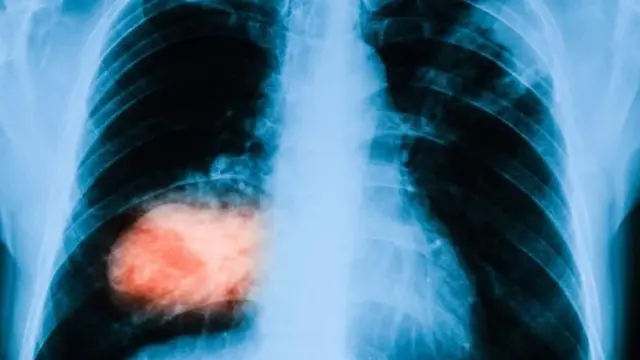

Dhibeen kaansarii gosa hedduu qaba. Isaan keessaa kan baay'inaan babal’achuun dhiiroota qofaa miidhaa jiru, piroosteet (prostate) kaansariin tokko.

Odeeffannoon Kaansarii addunyaa (Global Cancer Statistics) akka ibsutti, bara 2020tti qofaatti namoota haaraa 1,414,259 ta’utu dhukkuba caansarii piroosteetii kanaan qabaman.